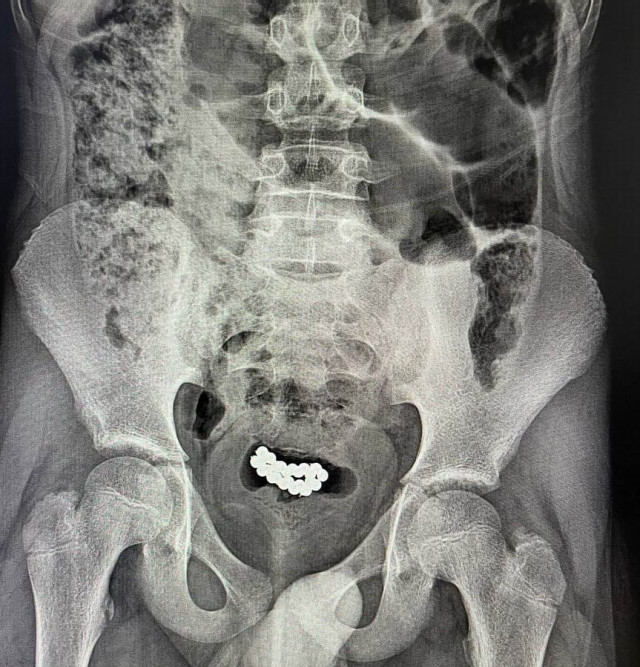

У Луцьку з сечових міхурів двох хлопчиків дістали понад 80 магнітних кульок

За останні три місяці в нашому закладі успішно було прооперовано два ідентичні випадки евакуації магнітних кульок з сечового міхура хлопчиків віком 10-15 років. В обох випадках було виконано цистотомію міні-лапаротомним доступом з подальшим вилученням 62 та 24 магнітних кульок.